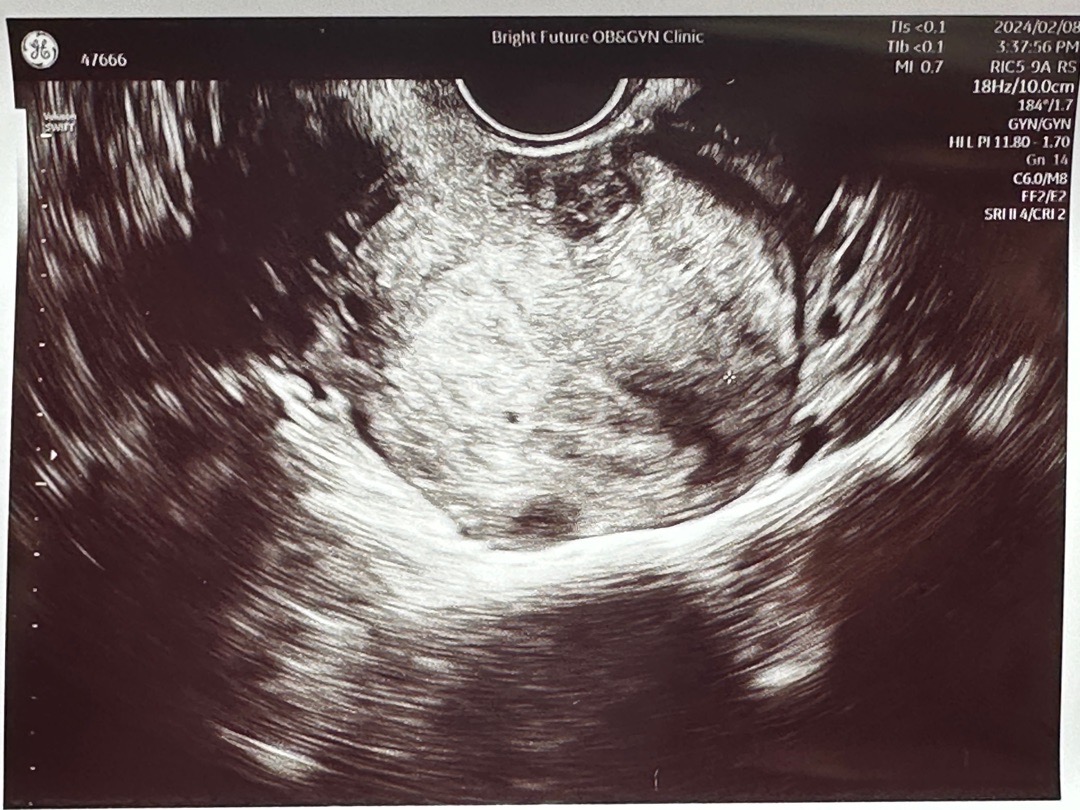

4주 5일차 초음파보고왔어요❣️

막생 1/6, 주기 28~30, 배란일 18일차 아직 넘 작아서 아기집으로 추정된다고 하셨어요! 다음주에 다시 초음파 찍었을때 사이즈가 커져야 한다고 하시더라고요! 임테기가 더 안진해진다고 말씀드리니, 진하기만 하면 되고 역전되는거는 넘 신경쓰지 말라고 하셨어요! 제발제발 좋은일만 가득하기를❣️❣️❣️❣️❣️